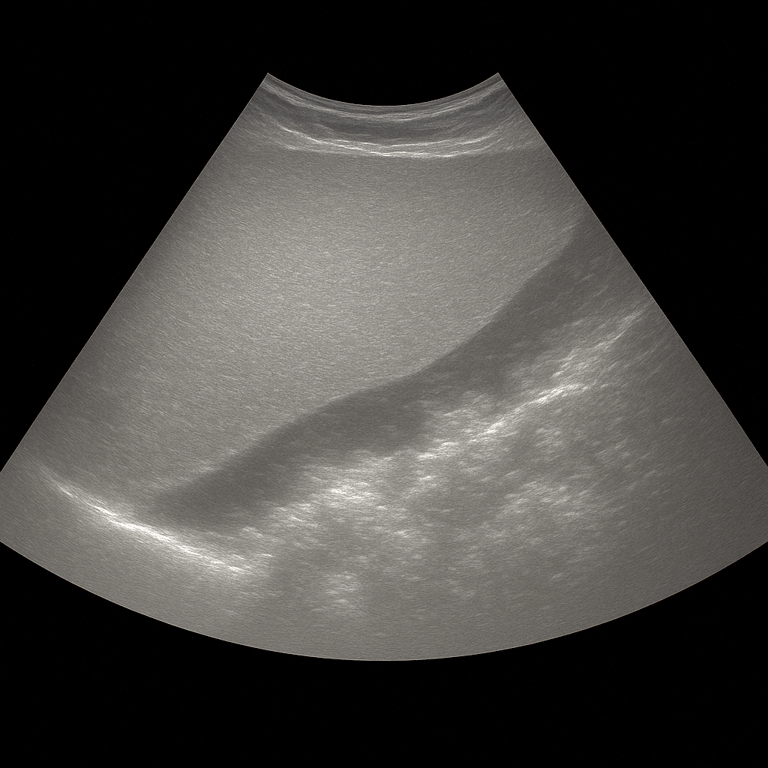

Ultrasound of the liver with elastography is a more advanced examination that measures the stiffness of the liver tissue to assess the degree of fibrosis or scarring in the liver. Unlike a standard ultrasound examination, which primarily shows the structure and appearance of the liver, elastography can quantify how hard or soft the tissue is – which makes it possible to detect signs of liver disease early before the changes are visible on the image.

The method is a gentle alternative to liver biopsy and provides an objective measurement of the elasticity of the liver. By measuring how quickly mechanical waves travel through the tissue, the doctor can determine how stiff the liver is – the stiffer the tissue, the more fibrosis.